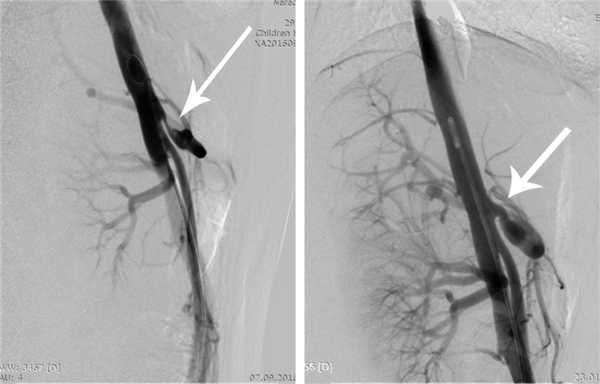

Ангиография является наиболее инвазивным и в то же время наиболее информативным в настоящее время методом, позволяющим подтвердить диагноз КСЧС, оценить степень и протяженность сужения ЧС и определить показания к хирургическому лечению. При ангиографии после пункции и катетеризации правой бедренной артерии всем больным выполняли целиакографию в прямой и боковой проекциях и аортографию. При этом изучали ангиоархитектонику ЧС и его ветвей, особенности строения и отхождения от аорты с измерением диаметра аорты, диаметра и протяженности стенозированного участка ЧС и диаметра постстенотического участка (рис. 2).

Рис. 2. Ангиограмма (целиакограмма) в боковой проекции. Стрелкой указано сужение устья чревного ствола более 80%.

Двум пациентам проведено контрольное обследование в позднем послеоперационном периоде: УЗИ в режиме импульсно-волновой допплерографии, МСКТ с внутривенным усилением (рис. 5) и ангиография (рис. 6). Клинически в обоих наблюдениях отмечалось уменьшение интенсивности, частоты и продолжительности болевого синдрома.

Рис. 6. Ангиограмма (целиакограмма) в боковой проекции до (а) и после (б) операции.